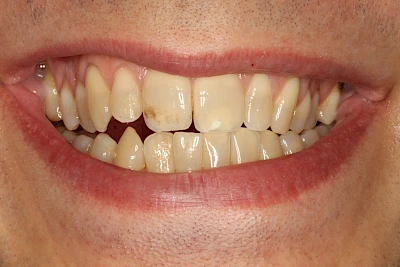

- Durch übermäßige Fluorideinlagerung in der Zahnreifung (mehrere Zähne, weißlich-fleckig)

- Durch Medikamente während der Zahnreifung (einzelne Zähne auf beiden Seiten, z. B. bläulich durch Antibiotikum Tetrazyklin)

Manche Medikamente wie zum Beispiel das Antibiotikum Tetrazyklin kann bei Einnahme im Zeitfenster der Zahnentwicklung auch irreversibel in die Zahnsubstanz. eingelagert werden. Tetrazyklin verfärbt die jeweils betroffenen Zähne bläulich und sollte deshalb während der Schwangerschaft und bei Kindern nicht verordnet werden.